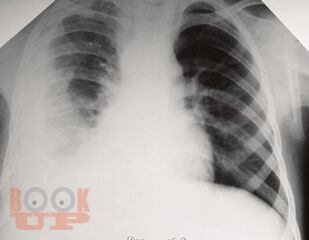

В учебно-методическом пособии отражена характеристика такого инфекционного заболевания как туберкулез, которое по-прежнему остается серьезной проблемой во всем мире. Дана характеристика основных групп риска развития туберкулеза, так как в группах риска заболеваемость туберкулезом в несколько раз выше, чем среди остальной части населения Российской Федерации и Ставропольского края. В пособии дано определение состоянию латентной туберкулезной инфекции, и подробно изложены методы ее диагностики. Также отражены основные направления профилактических мероприятий среди всех возрастных категорий, позволяющие снизить напряженность эпидемической ситуации по распространению туберкулеза.